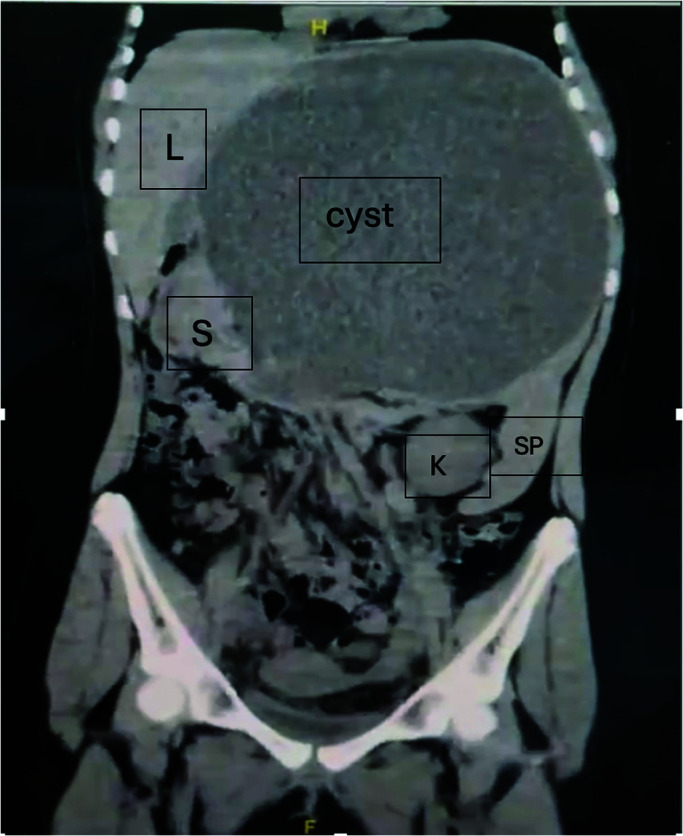

Case presentation: A 12-year-old female patient presented with a visible upper abdominal, painless cystic lesion, underwent blood tests and radiological diagnostic tools, such as abdominal ultrasound and computed tomography (CT) scan, but no definite diagnosis could be reached. Ultrasound-guided aspiration of the cyst was done, followed by explorative laparoscopy with total excision of the cyst (which was found to originate from the spleen), accompanied by partial splenectomy. The cyst was diagnosed as a benign primary mesothelial cyst of the spleen by histopathology. The patient experienced an uneventful postoperative period and showed no recurrence during follow-up.